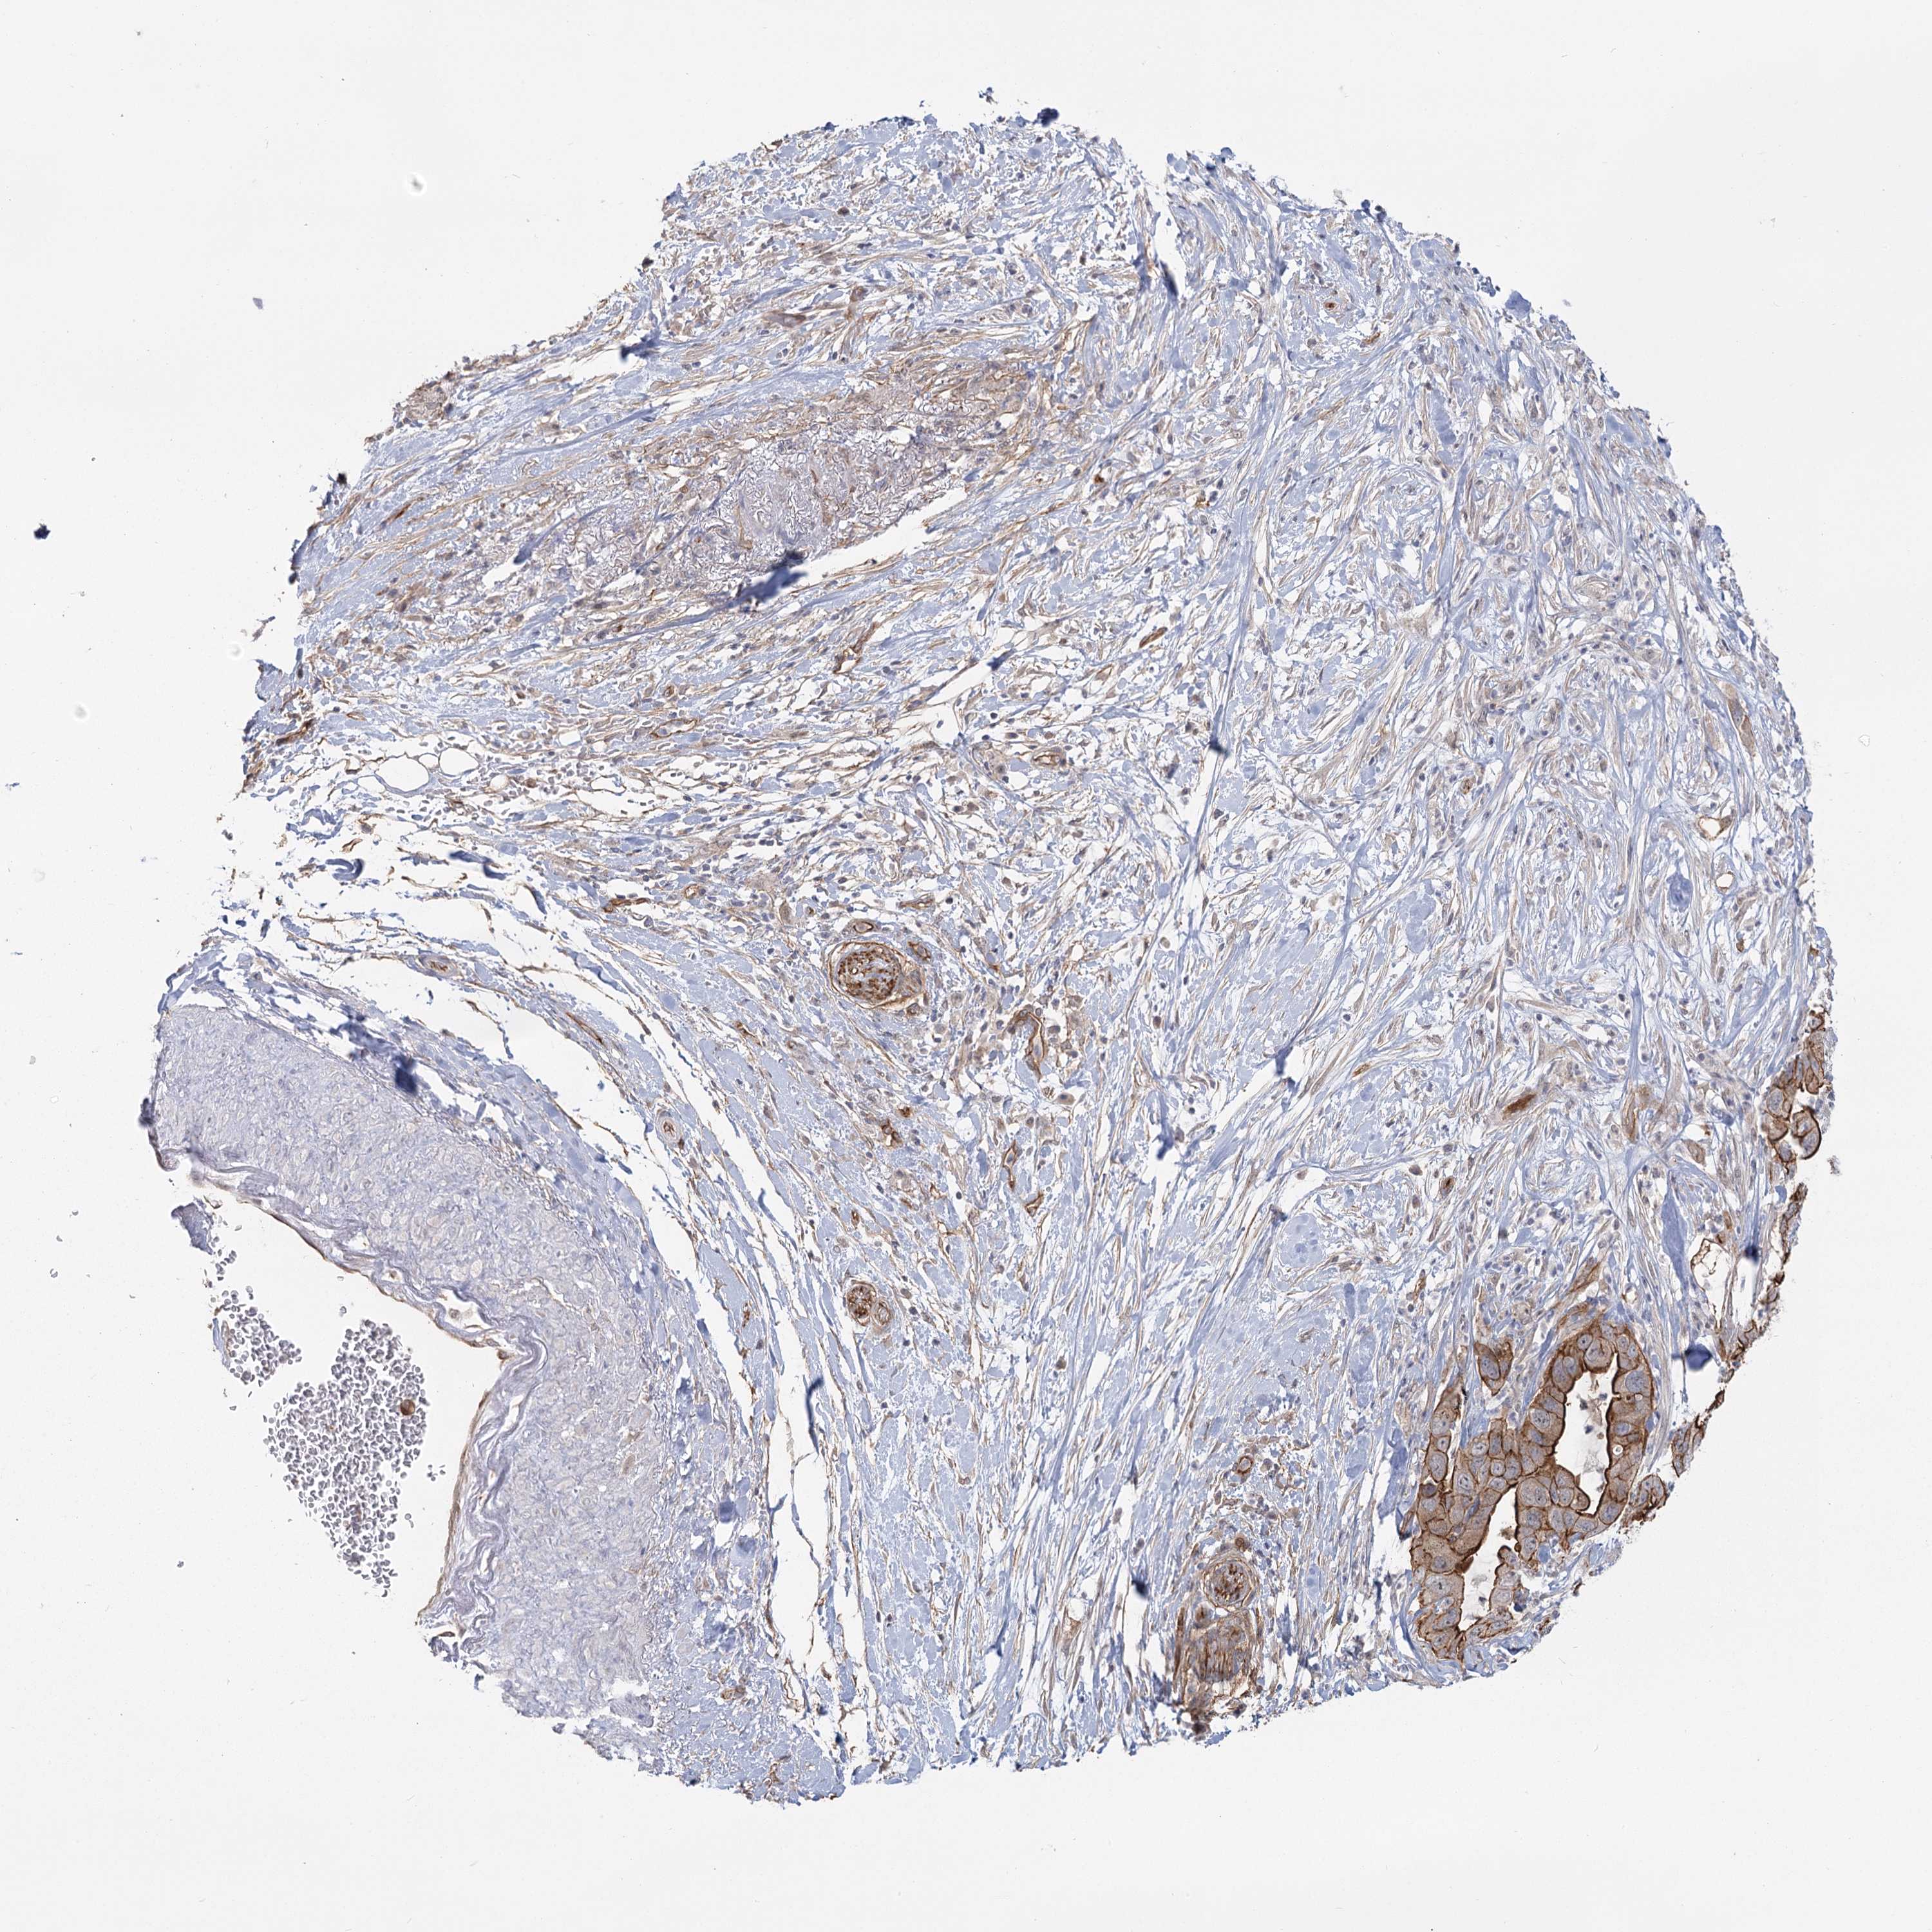

PANCREATIC CANCER - Protein expressioni

A mouse-over function shows sample information and annotation data. Click on an image to view it in a full screen mode. Samples can be filtered based on level of antibody staining by selecting one or several of the following categories: high, medium, low and not detected. The assay and annotation is described here.

Note that samples used for immunohistochemistry by the Human Protein Atlas do not correspond to samples in the TCGA dataset.

Antibody stainingi

Antibody staining in the annotated cell types in the current human tissue is reported as not detected, low, medium, or high, based on conventional immunohistochemistry profiling in selected tissues. This score is based on the combination of the staining intensity and fraction of stained cells.

Each image is clickable and will lead to virtual microscopy that enables deeper exploration of all samples and also displays staining intensity scores, fraction scores and subcellular localization as well as patient and tissue information for each sample.

Antibody HPA036194

Staining

High

Medium

Low

Not detected

Intensity

Strong

Moderate

Weak

Negative

Quantity

>75%

75%-25%

<25%

None

Location

Nuclear

Cytoplasmic/membranous

Cytoplasmic/membranous,nuclear

Adenocarcinoma, NOS